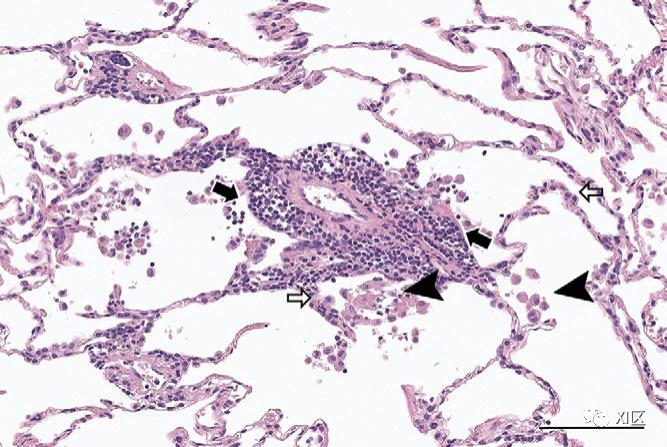

在大多数情况下,轻度新冠肺炎患者的病程是可逆的,不会发展为ARDS。因此,先前描述的炎症过程不会继续并破坏肺泡血管基底膜。相反,早期新冠肺炎的组织病理学结果通常表现为非特异性肺炎或机化性肺炎模式(图3):II型肺细胞增生、间质炎症、蛋白渗出的肺泡内水肿和最终组织(ultimate organization),但无纤维蛋白或透明膜,仅有少量纤维化。渗漏的炎性细胞和纤维蛋白的沉积可以短暂形成肺泡内组织成纤维细胞组织,但最终通过上皮细胞增殖得到解决和重塑。

图3:一例53岁男性早期轻度新冠肺炎偶然组织病理学发现的代表性病例。该患者因肺腺癌接受了右上叶切除术和纵隔淋巴结清扫术。术后一周,患者出现高烧和咽喉痛,经实时PCR检测证实患有COVID-19。提取的右上叶标本经苏木精和伊红染色后显示出潜在的早期新冠肺炎组织病理学发现:肺泡壁局部扩张伴炎性细胞浸润(黑色箭头),II型肺细胞增生(白色箭头),以及空腔中的一些肺泡巨噬细胞(箭头)(标尺:100μm)。患者病情好转,出院后无临床或放射学恶化。根据这些组织病理学发现,与机化性肺炎相一致的CT模式是轻度新冠肺炎患者的主要特征(图4)。事实上,高达50%-70%的轻度新冠肺炎患者经常报告有外周或支气管血管周围分布的GGO和小面积的实变,代表了CT上的机化性肺炎模式。当然,肺实质纤维化可能表现为机化性肺炎的CT表现之一,如小叶周围增厚、牵引性支气管扩张或局灶性体积减少。其他报道的轻度新冠肺炎患者的CT特征包括GGO伴间质增厚(即疯狂铺路征外观)、小叶周围GGO和反晕征。轻度新冠肺炎的这些CT特征相对难以与隐源性机化肺炎或继发性机化性肺炎模式与其他原因区分开来,例如流感肺炎,提醒我们机化肺炎模式并非新冠肺炎特有,而是对肺损伤的一般反应。